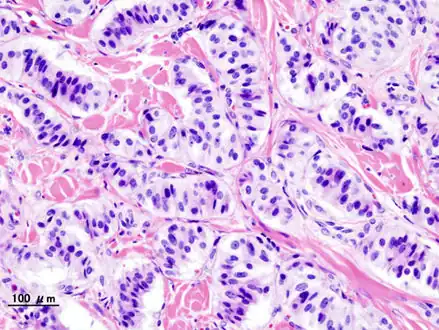

| Pathology of pancreatic endocrine tumour (insulinoma). | |